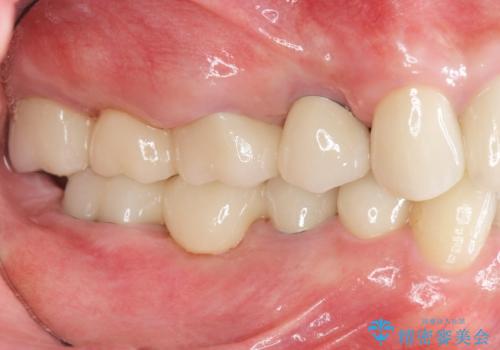

矯正治療を絡めた総合的な治療をお行なったことで、理想的な咬合関係を確立し安定した噛み合わせで仕上げることができました。

また歯周外科を行うことで歯ぐきの腫れを改善し、清掃性を高めています。